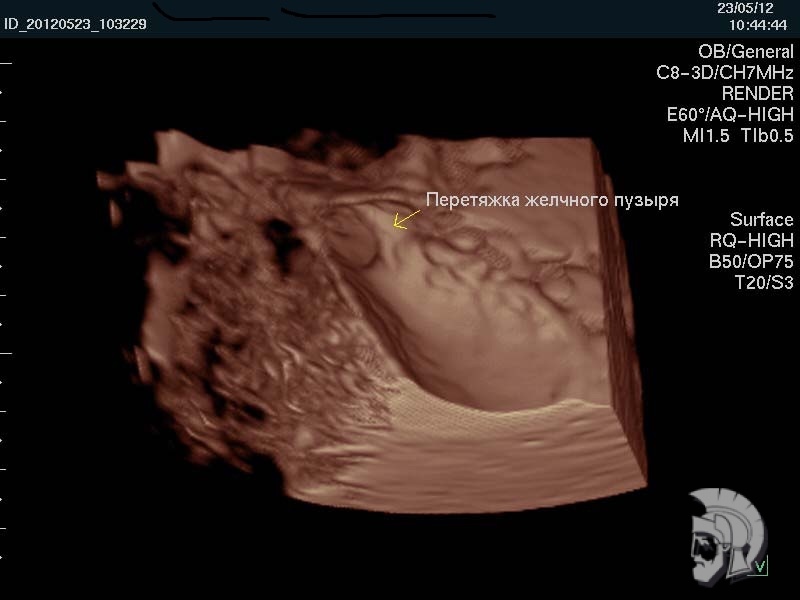

| 3D-фото желчного пузыря. Тот же случай |